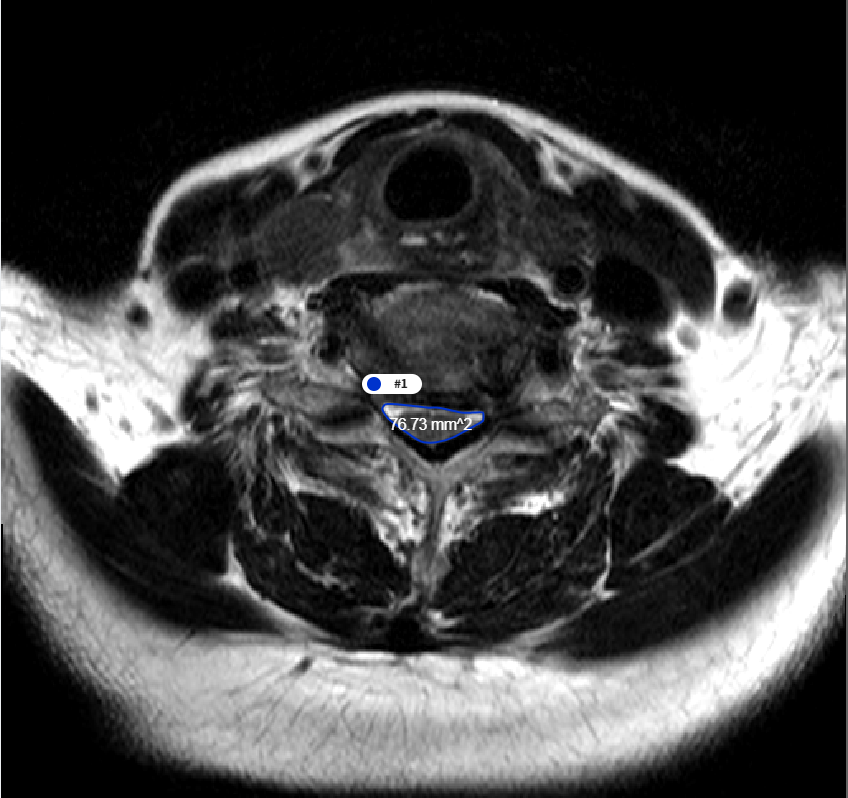

3. T2 Axial에서의 척수 영역 분할 및 면적 측정 모델

- 모델 학습

- 바이오 의료 영상 분야에서 분할을 목적으로 만들어진 모델을 사용하여 학습을 진행.

- Erode 및 Dilate, Median Blur를 이용해 이미지 후처리. Noise 및 Hole 제거

[T2 MRI에서 척수 영역 분할 모델 개요]

- 척추 면적 측정

- Dicom Header의 Pixel Spacing 정보를 통해 AI 결과에 대한 면적(mm2) 측정

[척추 영역 면적 측정]

데이터 성능 지표 번호 측정항목 AI TASK 학습모델 지표명 기준값 점수 측정값 점수 1 척추 면적 측정(T2 Axial) Object Detection U-Net Correlation 0.75 단위없음 0.83 단위없음 2 디스크 높이 측정 Object Detection U-Net, Attention U-Net Correlation 0.7 단위없음 0.71 단위없음 3 척수 영역 분할(T2 Axial) Image Classification U-Net DSC 0.8 단위없음 0.95 단위없음 4 요추 분할 결과 Image Classification U-Net, Attention U-Net DSC 0.85 단위없음 0.92 단위없음 5 후종인대 골화증 영역 검출 모델 Object Detection YOLO Sensitivity 75 % 81 %

대표도면 데이터 종류 예시 데이터 종류 경추x-ray 흉추 MRI 흉추CT 예시

데이터 구성 경추 디스크의 높이

경추 각 추체에 대한 bounding boxT2 axial image에서 흉추5-6번 구간의 면적

T2 axial image에서 척수 영역에 대한 외곽선흉추골화증평가